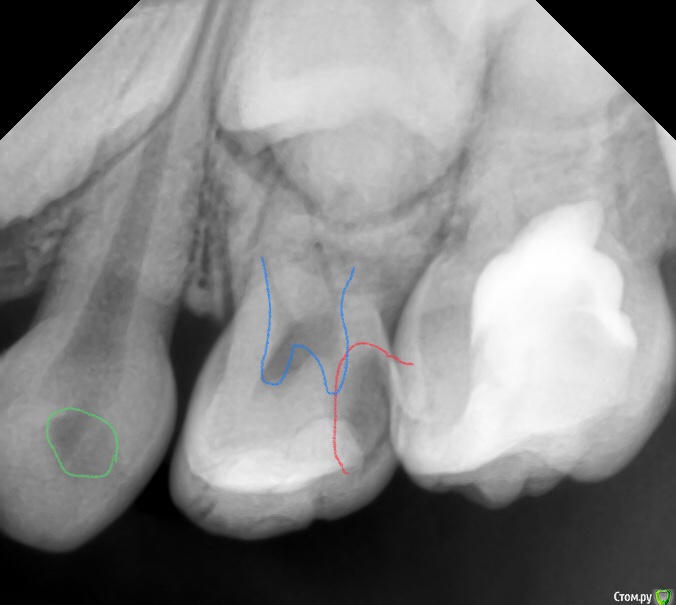

CRAZYDUCK Опубликовано 30 мая, 2018 Автор Поделиться Опубликовано 30 мая, 2018 Про обратимый пульпит .( ампутацию) Лечение методом витальной АМПУТАЦИИ. Даше в июле 6 лет . Познакомились мы полтора года назад , но сотрудничать не получилось , направлены для лечения в условиях общего обезболивания ( наркоз ) к ☺ @toothfairymila После лечения в условиях наркоза дети легче идут на контакт . Ребёнка не узнать - если до лечения в наркозе Даша даже в кресло садилась со слезами , то после - милые подарки , осторожно , но готова сотрудничать . Даша внимательно смотрит на моих ассистентов , взгляд изучающий ( можно этому человеку доверять или нет ). Маме Даши огромное спасибо - очень ответственно относится к регулярным осмотрам . Выявили скрытые кариозные полости и Даша доверилась лечиться в обычных условиях ( без наркоза ). 6.4 - обратимый пульпит , изначально было обширное разрушение , восстановлено пломбой в наркозе , поэтому лепить там пломбу ещё больше нет смысла. После ампутации -спонтанный гемостаз ( сравните с предыдущим случаем). Промываем ХГ 2% , мта на устья , IRM , коронка. 6.5 - обширная реставрация окклюзионно и начался кариес на медиальной контактной поверхности . Зуб должен меняться примерно в 10 лет ( 9-11 лет средний срок), то есть хочется , чтобы он постоял ещё года четыре , поэтому покрываем коронкой . Ждём Дашу на осмотр через 3-4 месяца.П.С. На заметку молодым коллегам - На снимке обвела зелёным нерентгенконтрастную реставрацию на зубе 6.3 , похоже на кариес , но это очень хорошая реставрация ! 1 Ссылка на комментарий